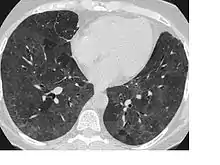

Ground-glass opacity seen on CT caused by hypersensitivity pneumonitis, not flock worker's lung. This type of abnormality is commonly seen in flock worker's lung.

Signs and symptoms of flock worker's lung include rales (crackling noises caused by fluid in the lungs), dyspnea (shortness of breath), and coughing. Abnormalities seen on a computed tomography (CT) scan of the lungs can include ground glass opacity and reticular opacity. The typical histopathology in flock worker's lung is bronchiolocentric interstitial pneumonitis and lymphocytic bronchiolitis with lymphocytic hyperplasia. Occasionally, desquamative interstitial pneumonia and bronchiolitis obliterans organizing pneumonia can be seen.[3][4]